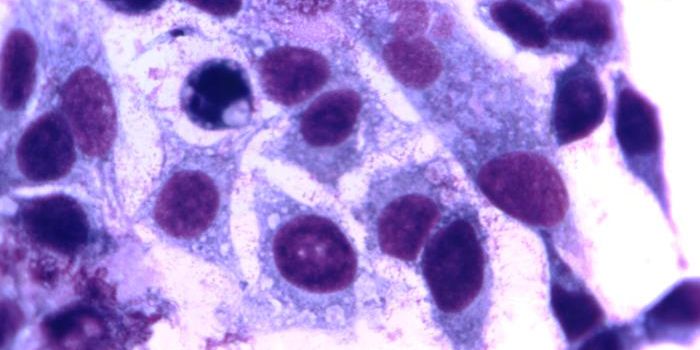

JUN 30, 2016Genetics & GenomicsIn the world of malaria infection, Plasmodium falciparum parasites will always be queen to their less lethal cousin, Pla ...